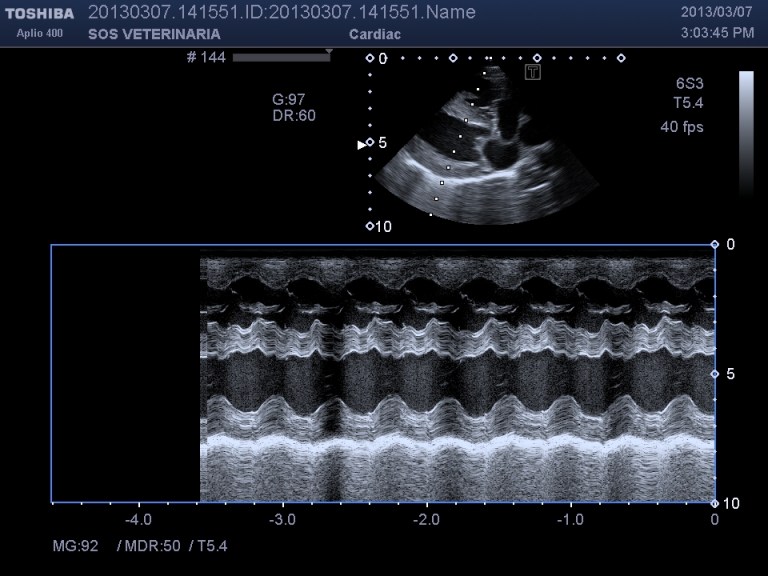

Ecco i filmati piu’ significativi osservare il flusso laminare che scorre parallelo alla parete laterale dell’arteria polmonare non piu’ continuo ma annullato in sistole dalla gittata in polmonare ,nel terzo filmato si vede l’ampolla del dotto